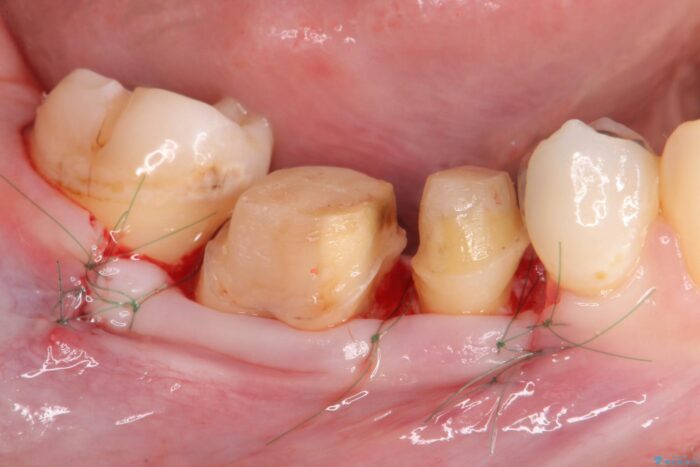

虫歯を丁寧に除去し、歯周外科を用いて周囲の歯ぐきの炎症を除去します。その後、清掃性の高い精密なセラミック治療をおこなっていきます。

歯ぐきの炎症も治まり、疼きなどの違和感もなくなりました。